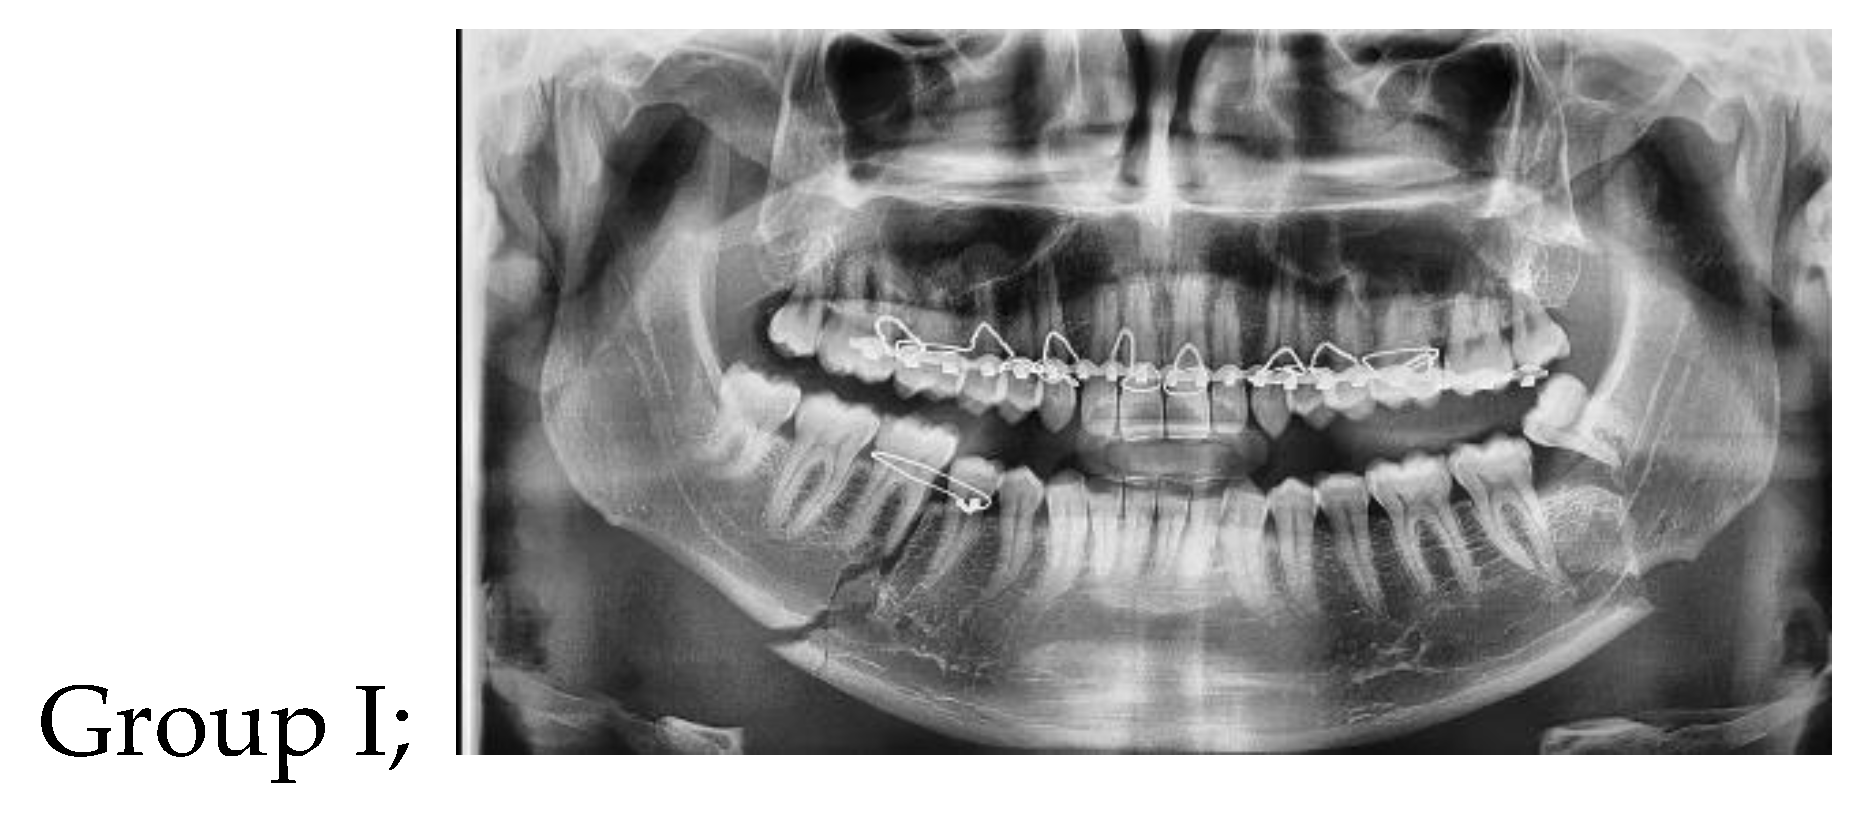

Figure 1. Photoradiograph of panoramic view showing displaced left mandibular angle and right body fracture1.

Group I: eight patients treated with 3D curved angle plate.